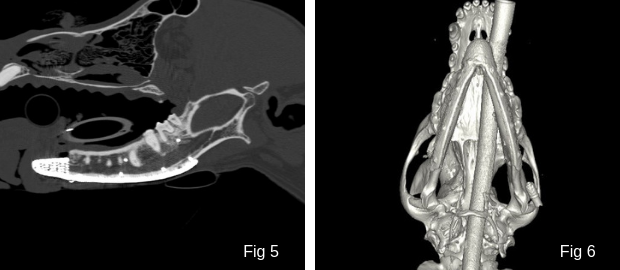

Fig. 5 & 6: CT scans showing the reconstruction of the jaw with a 3D printed titanium patient-specific implant